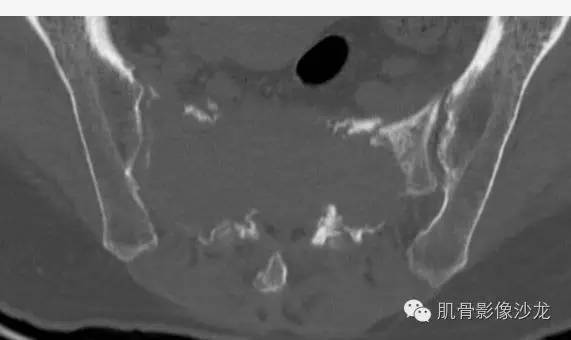

女,50岁,腰痛伴左下肢放射痛4个月

骶骨巨大骨质破坏区,破坏区软组织肿块密度较均匀,边缘不规则残留少许骨皮质,膨胀性改变不明显,肿块基本局限于骨破坏区内。

最后病理:高分化浆细胞瘤

这个溶骨性骨质破坏征象,骶骨的形态还是保留的 所以影像也像浆细胞瘤 但是 转移瘤必须鉴别 转移瘤万能的模仿者

@王斌常德二院 不一定是硬化,有些是残存皮质,这例边缘髓样破坏很明显

有残留骨皮质

没看到到,高密度区都位于皮质或小关节区